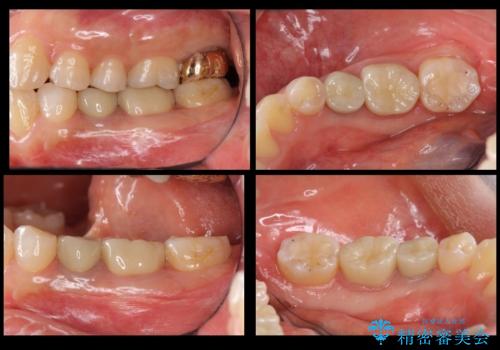

歯の高さがない 被せ物のやりなおし

- 左下の銀歯二本のやりかえを希望。(左下5および左下6)

高さがないため、歯肉と歯槽骨の手術(歯周外科手術)APFを行ってから、最終的な被せ物にしました。

手術後は半年仮歯で過ごしていただいた後、歯肉の高さが決まってからセラミッククラウンを装着していきます。